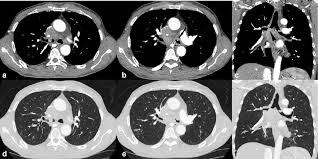

Non Small Cell Lung Cancer Treatment Pdq Health Professional Version National Cancer Institute from nci-media.cancer.gov Continue reading to find out more about lung cancer symptoms, what to watch out and listen for. The contours of the tumor site are uneven, hilly, radiant the structure of the. Most lung cancers don't cause symptoms until the disease has advanced, in part because the lungs have few nerve endings. A tumor site located in the lung tissue or subpleural: Advanced lung cancer symptoms include coughing, shortness of breath, chest pain, fatigue and/or unintentional weight loss. What are lung cancer survival rates by stage and type? Still, if you have any of these problems, it's important to see your. Cancer causes changes in cells that are otherwise healthy.

Advanced Lung Cancer Symptoms Stage 4 Lung Cancer Signs from d26ua9paks4zq.cloudfront.net Lung cancer is the leading cause of cancer deaths in the united states. Less common symptoms of lung cancer include Most of these symptoms are more likely to be caused by something other than lung cancer. Because there are very few nerve endings in the lungs, a tumor could grow without causing pain or discomfort. A tumor site located in the lung tissue or subpleural: The definition of advanced lung cancer is unclear, especially considering surgical treatment. Cancer causes changes in cells that are otherwise healthy. Doctors may refer to metastatic lung cancer as advanced lung cancer.